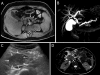

Objectives: Autoimmune pancreatitis (AIP) represents a complex immune-mediated pancreas disorder. Pediatric AIP (P-AIP) is rare. We have recently summarized the characteristic features of P-AIP. We now aim to develop recommendation statements to standardize the diagnostic and therapeutic approach to P-AIP and facilitate future research in the field.